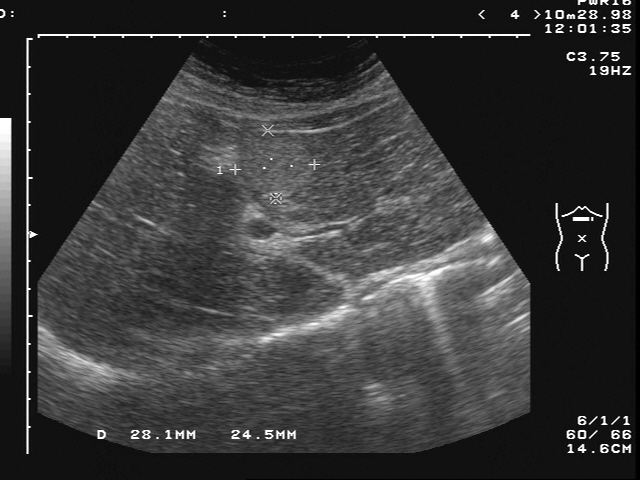

40多歲女性,家族史父親有併肝癌,近日因疲勞至診所就診。

進行腹部超音波檢查時,意外發現內有一血管瘤。

當病患知道肝臟內有腫瘤時相當緊張,經由醫師確認病患並無BC肝帶原,

並解釋超音波屬良性的血管瘤。

醫師建議於三個月後再次追蹤腹部超音波,

腹部超音波下腫瘤並無變化

告知之後可半年至一年追蹤一次腹部超音波